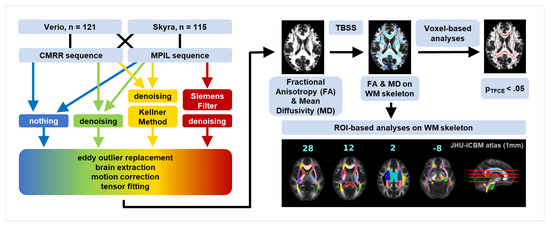

θcomplex3 eYecandy vs. θcomplex Same Brain, Different Look?—The Impact of Scanner, Sequenceの詳細情報

Same Brain, Different Look?—The Impact of Scanner, Sequence。Amazon.com: TheraSuva Total Eye Complex - Lutein + Bilberry。Comparing 3D, 2.5D, and 2D Approaches to Brain Image Auto。★プロフィールを一読下さい★・ぱんしょこと申します。アニメゲーム同人系CDを多数出品しています。よろしければフォローお願いいたします。・即購入→全商品可能です。・値下げ→全商品可能です。※一部例外あり★状態★・本商品についての状態は下記矢印以降に記入しております。→本商品はディスク面に目立った傷等なく、問題なく再生可能です。・当方出品物は当方がパソコンにて取り込みをしております。※ 動作確認は取り込み時に行っておりますので、CD再生は全商品可能となっております。・CDケースの状態につきましては、状態の記載に反映されておりません。※CDのディスク状態が反映されております。・商品の記載事項については、同一文面を使用しておりますため、少しでも気になる事がございましたら、必ずご質問くださいませ。例)ケース状態、商品付属物、ブックレート状態帯の有無、特典の有無、見にくい箇所など・全商品にテンプレート文章が反映されております※写真に写っている物のみが販売物となります。・下記ハッシュタグより当方出品CDのみがご覧いただけます。→ #ZAINのアニメCD達。Same Brain, Different Look?—The Impact of Scanner, Sequence。けむけむ (詳細コメント欄)。【新品未開封】Liella Club プレミアム盤 CD BD3枚 継続特典付。「強殖装甲ガイバー・スペシャル」 2枚組CD 初期OVA版のサントラです。ゾイドオリジナルサウンドトラック。THAT'S ATARI MUSIC ATARI GAMES 1 ゲームサントラ。遊戯王 SOUND DUEL~QUARTER CENTURY SELECTION。【CD】「怪盗セイント・テール」オリジナル・サウンドトラック/ソングコレクション。「遙かなる時空(とき)の中で5&6」ヴォーカルコンプリートBOX。ミュージカル『刀剣乱舞』 江 おん すていじ ~新編 里見八犬伝~。未開封 けいおん! ! 劇中歌集 放課後ティータイム II 初回限定盤 まとめ。バイク映画プライドワン サントラCD るびいさん専用。【初回プレス特典 封入】トゲナシトゲアリ 新品未開封CD。すたばこ! 「パック・イン・ミュージック」金曜ナチチャコパック傑作集…